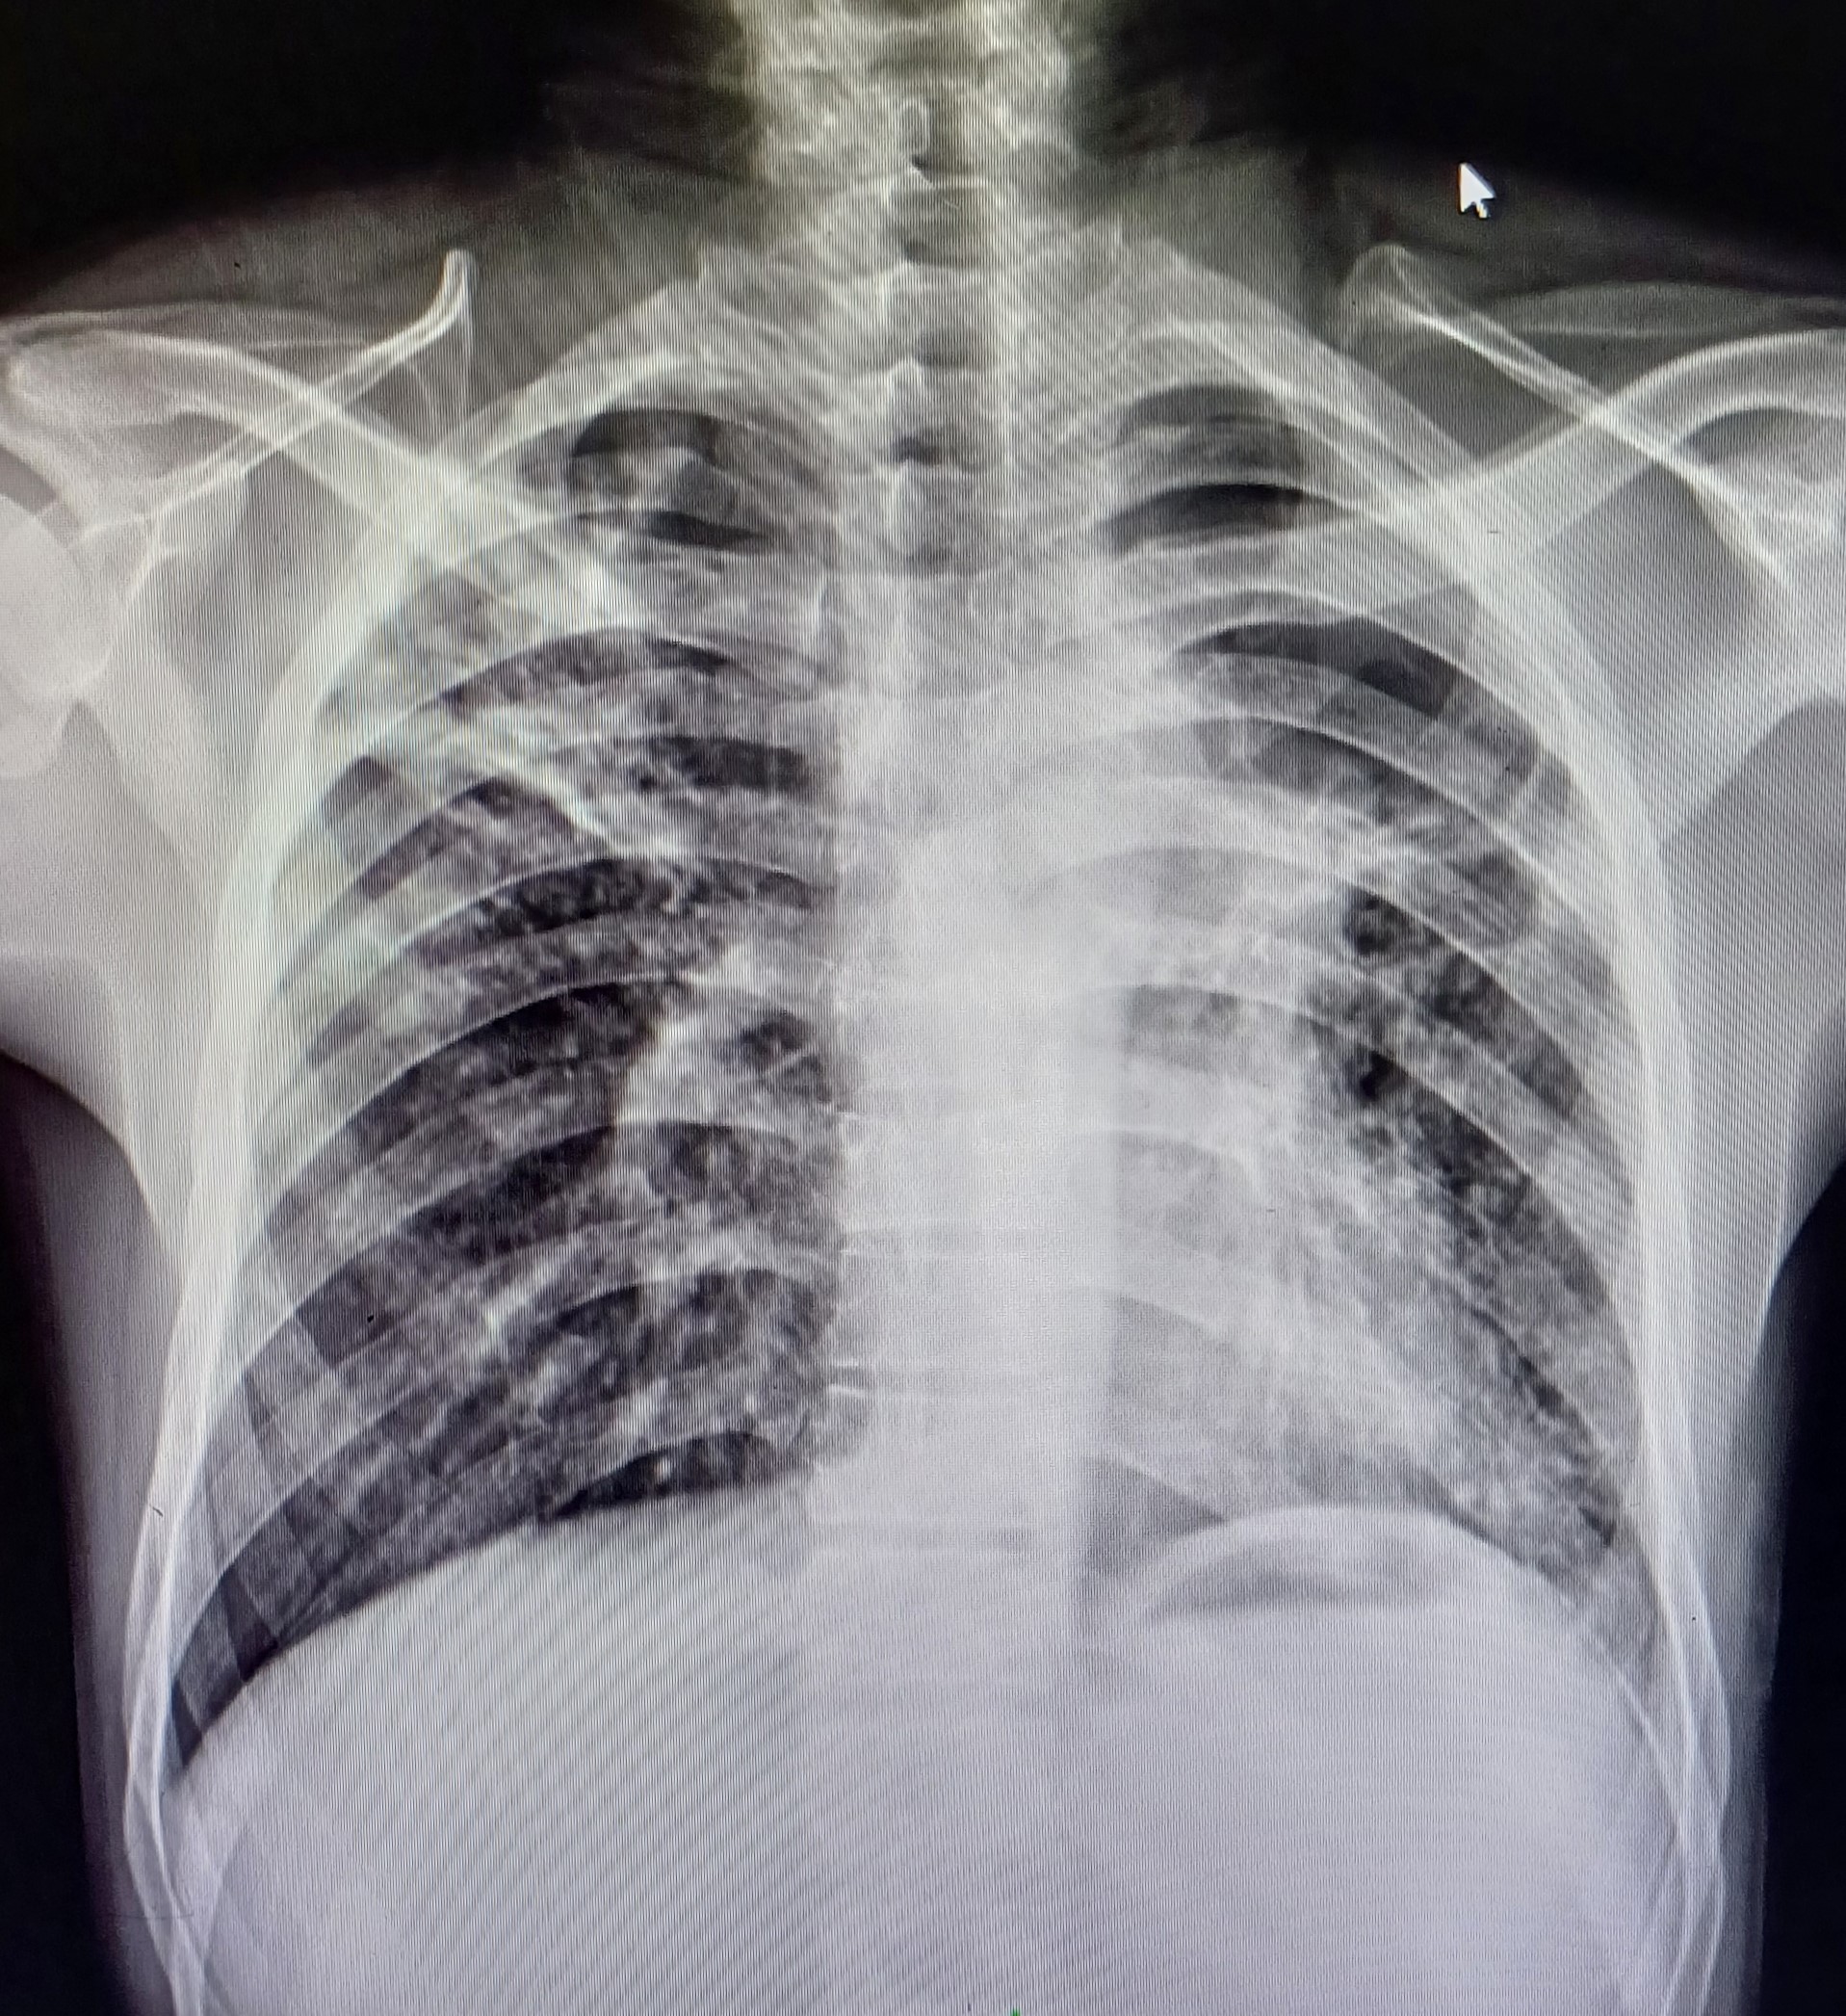

| 5 | IGGMC, Nagpur, Nagpur | P2 | 29-4467 | Meera Gohare | Consent taken on Paper | 64 Yrs. |

Provisional Diag : ?

Final Diag : Disseminated TB (Miliary TB With Abdomen Koch) |

TB Case (Confirmed) | Abnormality visible on x-ray |